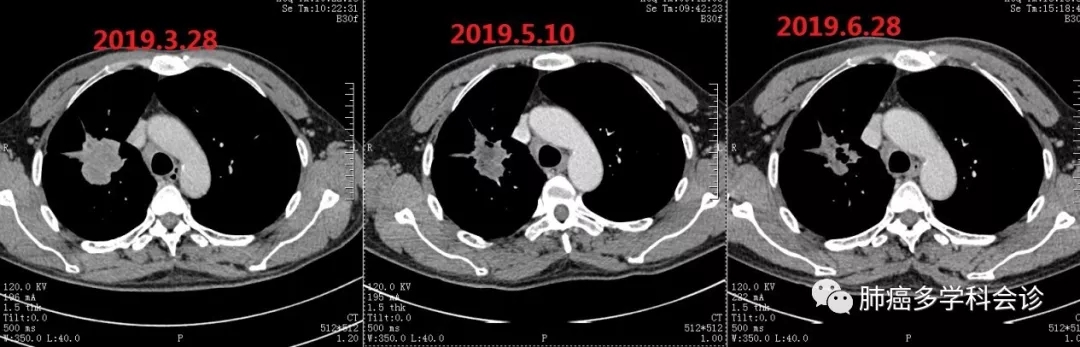

自2019.3.29起,在PD-1抗体(SHR1210)治疗基础上增加阿帕替尼口服,持续至2019-06-29。口服阿帕替尼后头面部和胸背部的反应性毛细血管增生症(过去称为樱桃样血管瘤)完全消退。体重恢复至患病前水平,PS 0-1分。肺原发灶进行性缩小:

5.webp.jpg患者2019-06月诉活动后前胸壁疼痛较前似有加重, CT示胸骨骨质破坏较前似有进展,以对胸骨病灶进行姑息性放疗后疼痛明显好转。